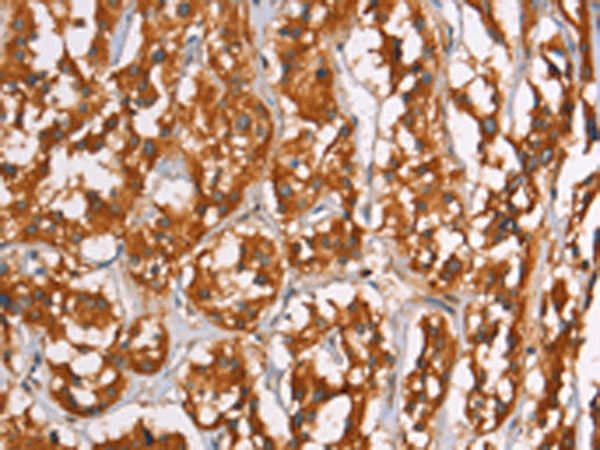

IHC positive control: |

Human thyroid cancer and Human tonsil |

IHC Recommend dilution: |

50-200 |